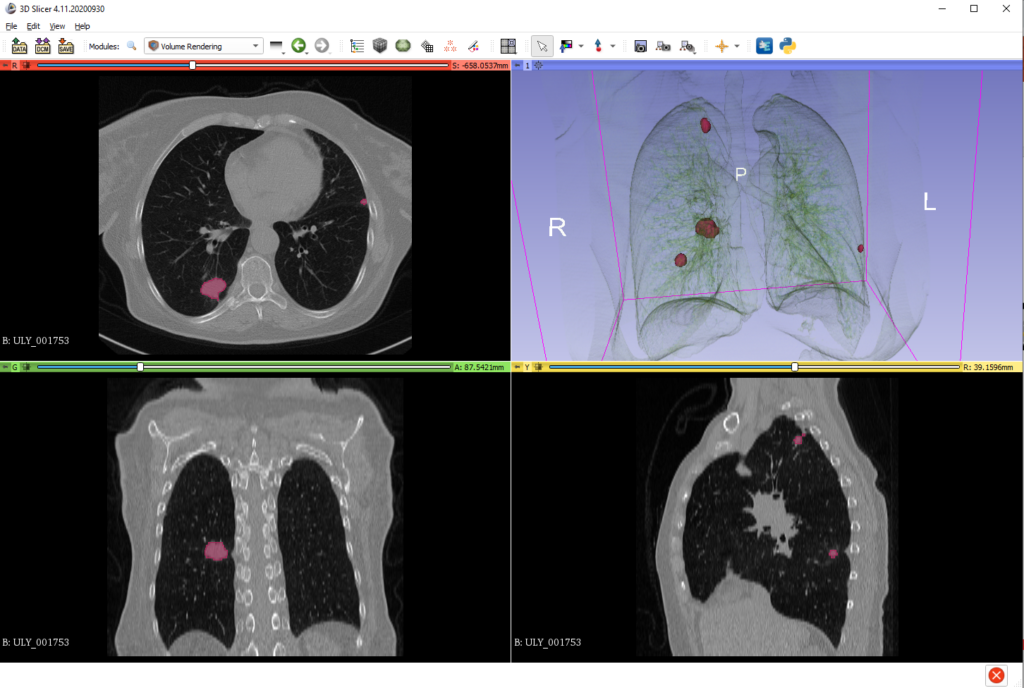

A szintén a Semmelweis Egyetem részvételével zajlott az a projekt, amely mellkasi CT felvételeket kiértékelő mesterséges intelligencia alkalmazásával segíti a daganatos megbetegedések korai felismerését. A neurális hálózatok mélytanulási módszerén alapuló most fejlesztett új diagnosztikai eljárás hatékonyabb szűréssel segíti majd a radiológusok munkáját.

Fotó: Semmelweis Egyetem